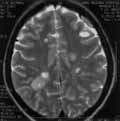

С двух сторон паравентрикулярно и субкортикально на Т2-взвешенном изображении

множественные разновеликие (размером от 0,5 до 2,0 см) округлые очаги,

дающие неравномерно повышенный МР-сигнал (Рис. 1). Аналогичные очаги

определяются в дорзальной части моста слева и в базальных отделах лобных

долей. В лобной доле субкортикально киста элипсовидной формы 1,2 х 0,5

см. На Т1-взвешенном изображении поля, выявляемые на Т2-изображении дают

слабо пониженный МР-сигнал или изоинтенсивны (Рис. 2); киста дает

гипоинтенсивный сигнал, четко контурируется. После введения магневиста

очаги, не визуализирующиеся на Т1-изображении, проявили себя равномерным

усилением МР-сигнала, другие дали усиление в виде ободка и небольшого усиления

в центре (Рис. 3).

Рис. 1. Т2-взвешенное изображение. С двух сторон паравентрикулярно и субкортикально множественные разновеликие гиперинтенсивные очаги. |